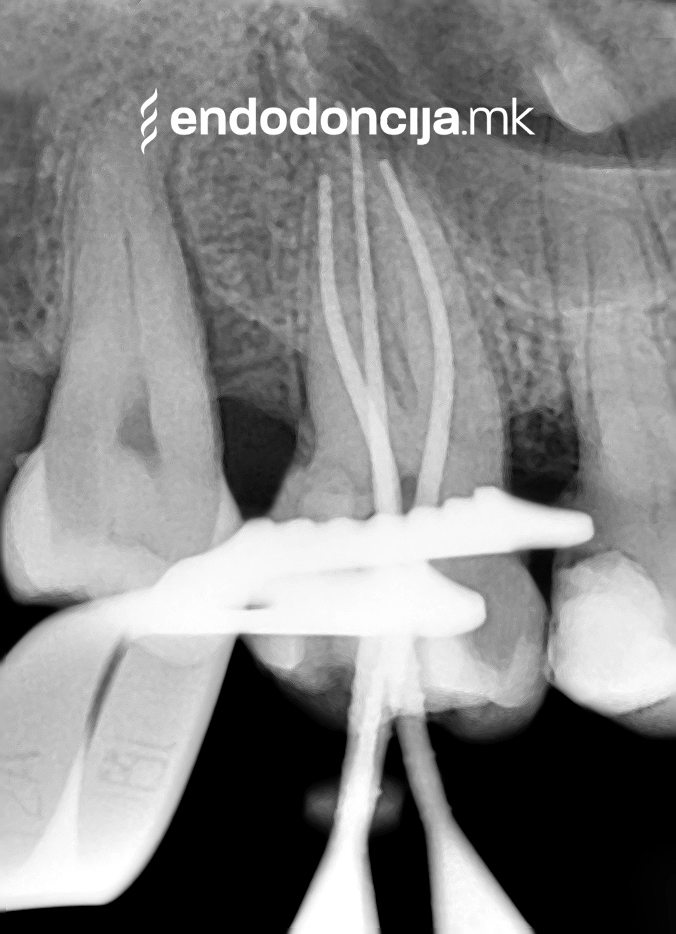

Современиот третман на коренскиот канал под микроскоп се трансформира во последните неколку години од обичен обид да се спаси забот до навремено лекување со многу висока стапка на успех. Евентуалното предвремено губење на забите сега може успешно да се избегне.

На специјализираниот оддел за ендодонција, нашите пациенти ги лекуваме на највисоко професионално и дијагностичко ниво. Опремени сме со најсовремени хируршки микроскопи, кои поддржуваат детален приказ и подготовка на коренот и нудат комплетно ново ниво на прецизност. Најновата ендодонтска опрема, инструментите и материјалите за полнење се во секојдневна употреба. На овој начин третманот станува пократок, дури и во комплицирани случаи, и се избегнува губење на забите.

Она што е импресивно е прецизноста на микроскопските третмани. Дури и кога каналите се потешко достапни, може да се лоцираат и исчистат така што релапсите се со помала веројатност. Спротивно на тоа, скриените канали често остануваат неоткриени во конвенционалниот третман на коренскиот канал и затоа не можат да се чистат. Бактериите можат да се размножуваат таму без пречки и да предизвикаат воспаленија. Ова често останува незабележано со години додека не се појави забоболка, а со тоа и компликации.